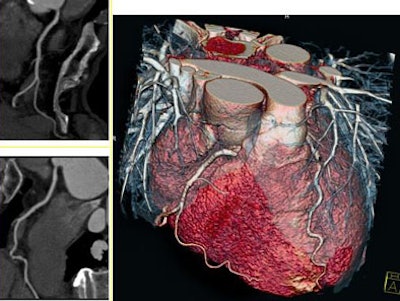

| Heart-rate-independent imaging with dual-source CT (DSCT). Coronary CTA images were acquired without beta-blockers at a heart rate 90 bpm. Temporal resolution of 83 msec, spatial resolution of 0.33 mm, six-second scan for 138-mm coverage, 0.33-sec rotation, and 120 kVp. Images courtesy of Nagoya City University Hospital in Japan and Dr. Gilbert Raff of William Beaumont Hospital in Royal Oak, MI. |